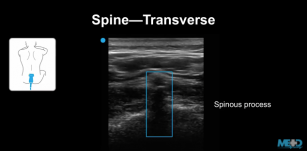

Identifying the lumbar spine on ultrasound. 24th Jan 2018 - Sara Damewood, MD Learn how to identify the lumbar spine and guide procedures using ultrasound.